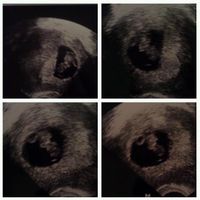

Baby's first pictures!!

Mrs. Wise, on December 12, 2012 at 12:49 AM

So we went for a ultrasound today it was so incredible we got to see our baby's heart flutter on the monitor and he or her little feet and hands wiggle.. He or she is upside down right now so his or...